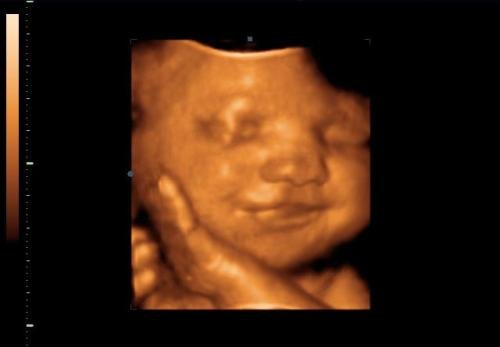

A méhecske is rájött a titokra, én pedig élvezem a zeneiskolából átszűrődő fuvolát, a gyerekek visítozását, a kislányom rugdalását a pocakomban. 🙂